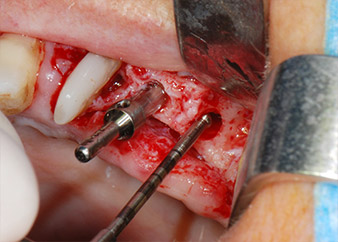

Zunächst wurde in einem Versuch, das Paro-Endo-Problem zu lösen, an der verbleibenden Wurzeloberfläche ein vorsichtiges Debridement mit einem piezochirurgischen Gerät vorgenommen (Piezomed, W&H) (Abb. 4); dann wurde der Apex mit dem gleichen Instrument im Sinne einer WSR abgetragen, um das verbleibende infizierte apikale Gewebe zu entfernen (Abb. 5). Eine retrograde Füllung war nicht notwendig, da die orthograde Füllung gerade revidiert worden war.

Brückenpfeiler

Abb. 4: Um den Zahn 24 als vorläufigen Brückenpfeiler zu erhalten, wird das Parodont mit einem piezochirurgischen Sytem gereinigt ...

bukkale Wurzelspitze

Abb. 5 ... und die bukkale Wurzelspitze mit dem gleichen Instrument abgetragen (WSR).